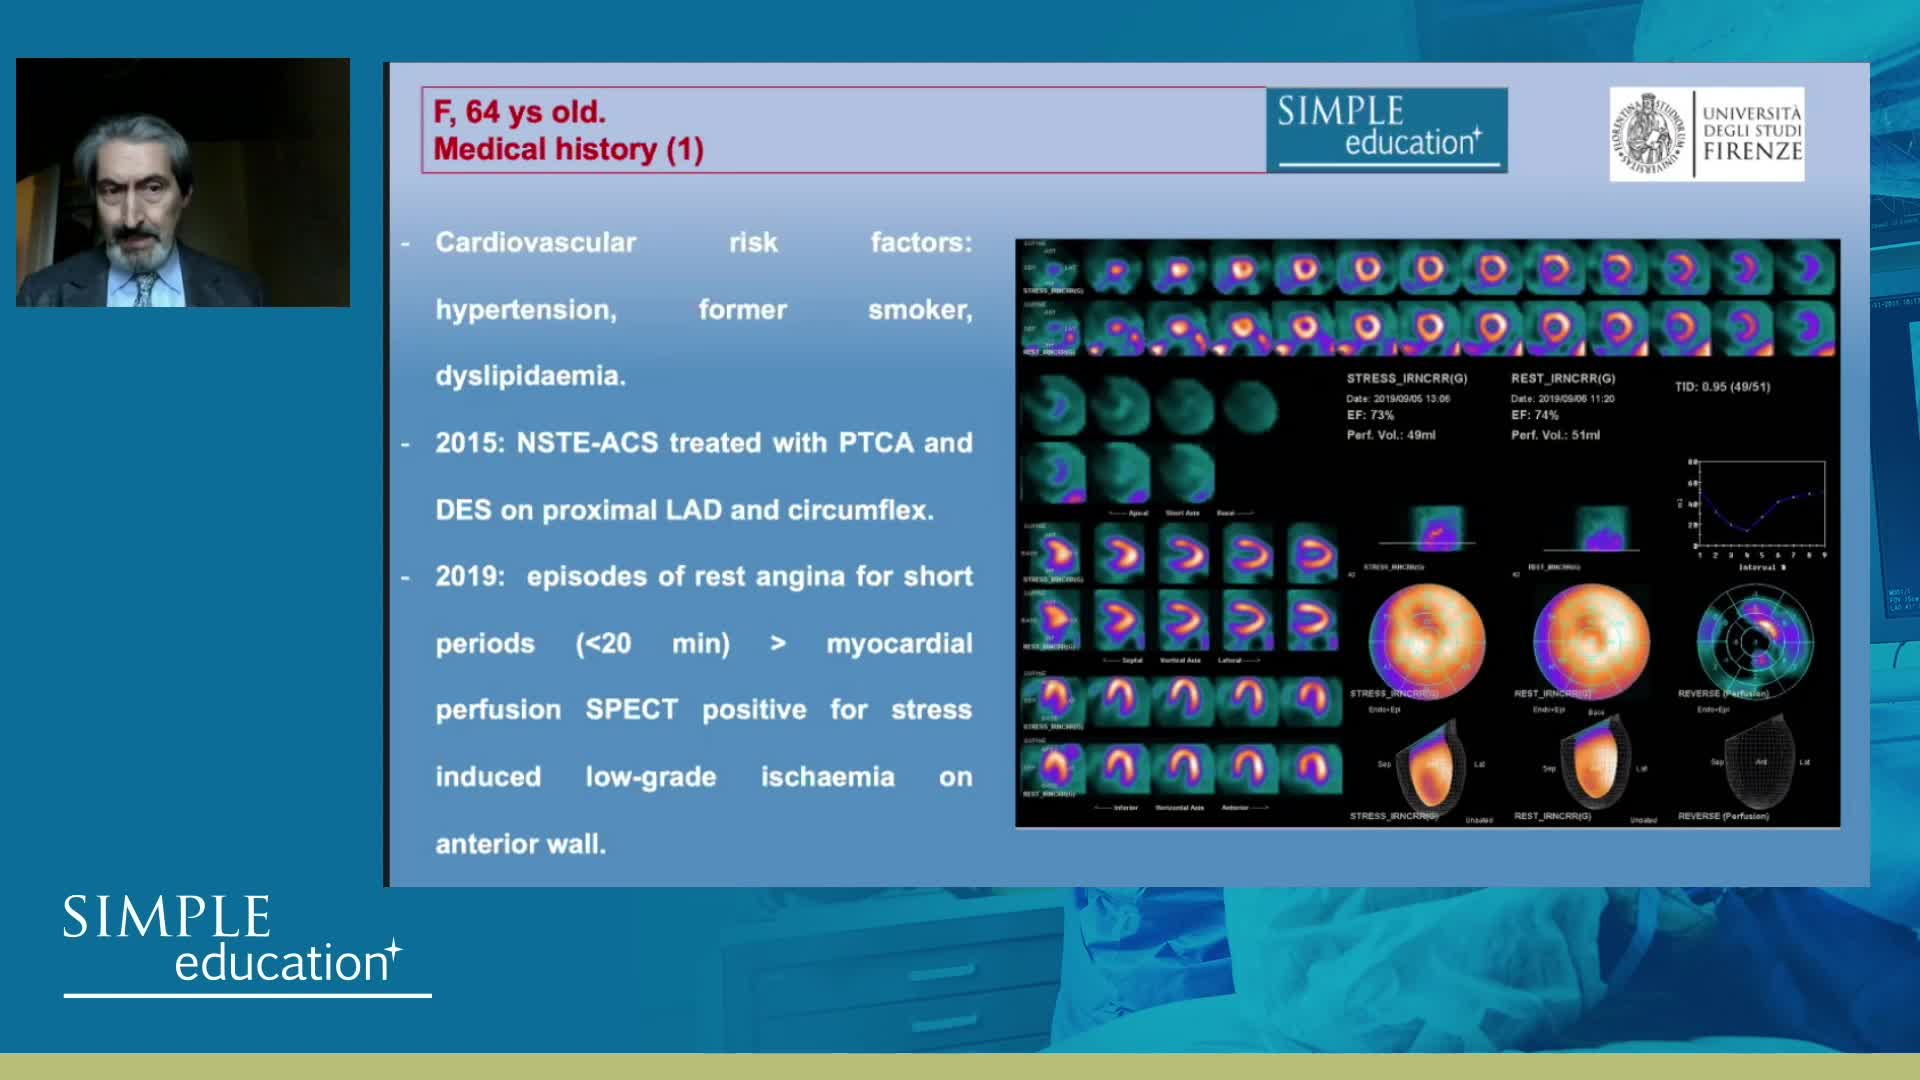

ABC for using Coronary Physiology in Aortic Stenosis, Primary Percutaneous Coronary Intervention (PPCI)/ACS, Muscle Bridges and Atrial Fibrillation - Dr Ricardo Petraco

Best practices and personalised medicine in complex PCI - Prof Javier Escaned

Functional assessment of coronary stenosis prior to TAVI - Prof Flavio Ribichini

Revascularisation in stable angina: a contemporary perspective - Dr Rasha Al-Lamee